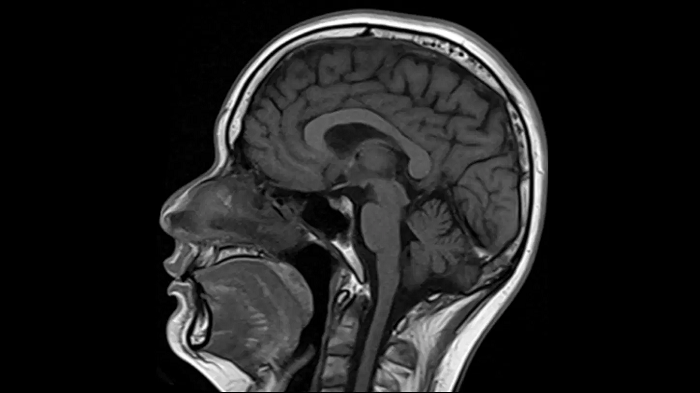

T1 SE

Outstanding T1 imaging with MAGNETOM Free.Star.

0.4 x 0.4 x 5.0 mm2

TA 2:38 minutes

MAC-ID: 7aaaa0195. Image Credit: Siemens Healthineers